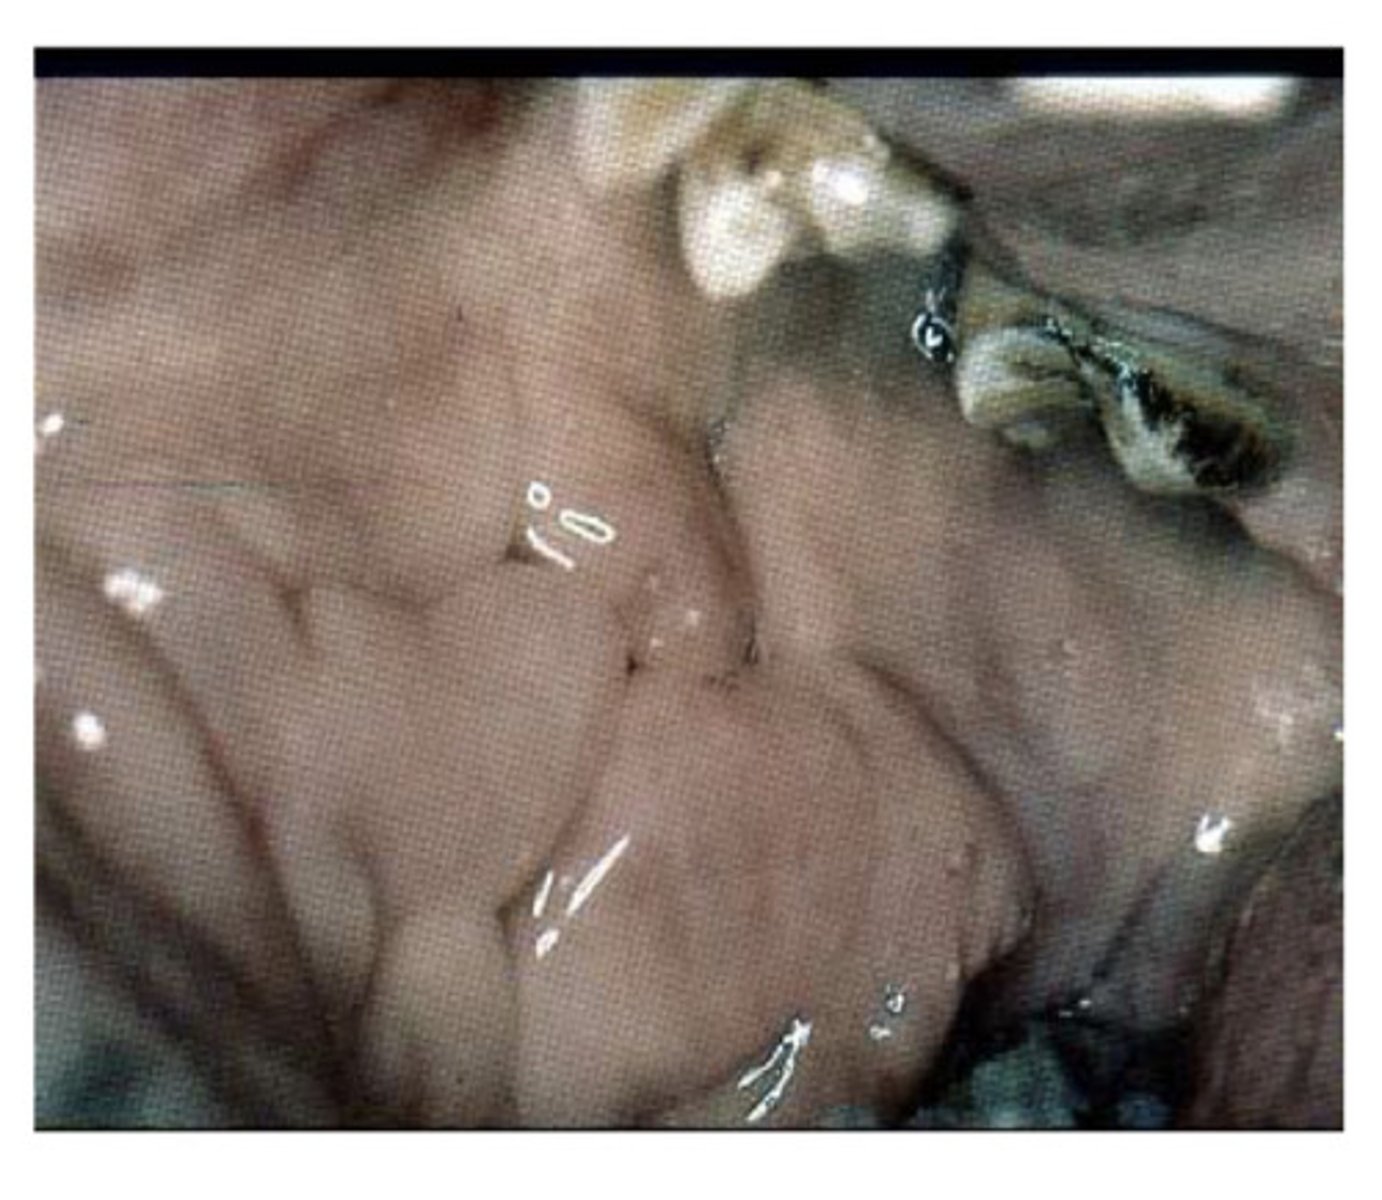

Cobblestoning caused by crohns disease

What is this and what is it caused by?